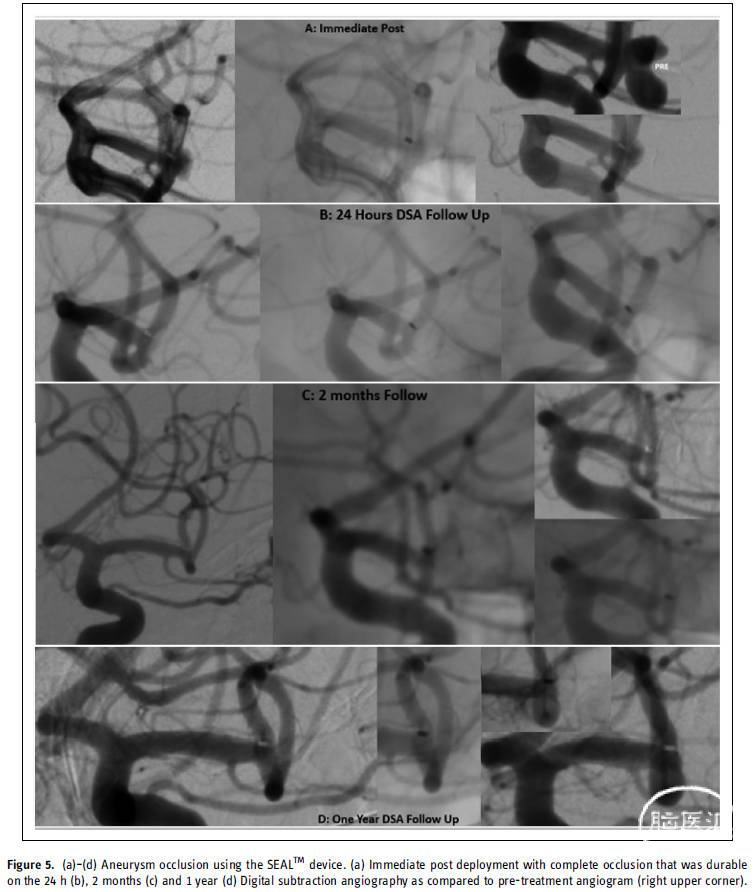

图5. 使用SEAL™装置成功闭塞动脉瘤。

SEAL™装置的部署和植入在技术上是可行的、安全的,并且很好地符合复杂破裂动脉瘤的不规则形状。植入后立即观察到动脉瘤完全闭塞。重要的是,术后1年的血管造影随访显示没有安全问题。